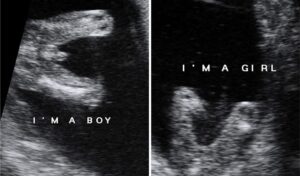

وفيما يلي بعض صور السونار التي يمكن ان تساعدك على التفرقه بين الاجنة الذكور والاناث في تصوير السونار.